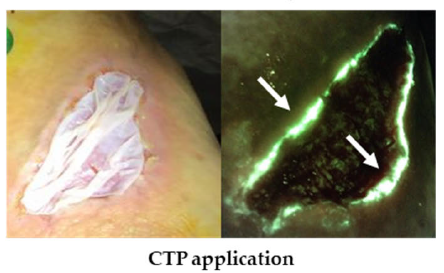

Efficacy and safety of a porcine peritoneum-derived matrix in diabetic foot ulcer treatment: a pilot study

Ai-Jalodi, O et al. J Wound Care 2021